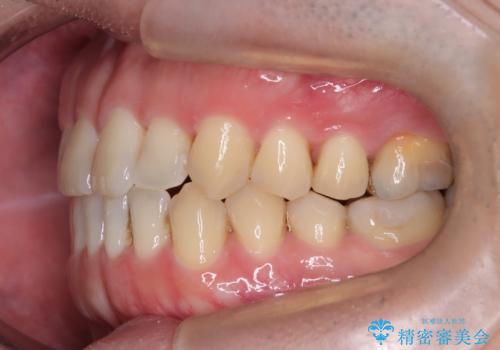

- 前歯の咬み合わせが気になるとのことで来院されました。

前歯が噛んでいない状態(開咬)のため、インビザライン矯正で改善することとしました。

前歯が嚙んでない場合(開咬)、顎間ゴムというゴムを使用してもらうことがあります。顎間ゴムは、前歯を噛み合わせるための力を与える補助的な役割があります。